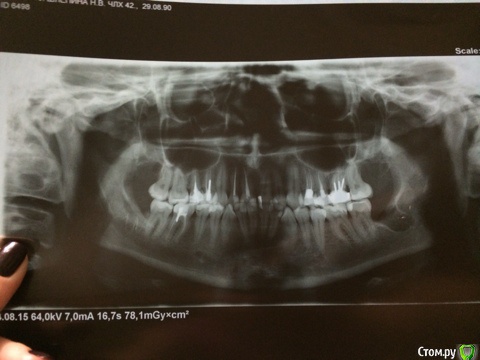

skazzkina Опубликовано 26 августа, 2015 Поделиться Опубликовано 26 августа, 2015 Здравствуйте, уважаемые врачи! Прошу консультации, после удаления всех восьмерок осталось уплотнение/похоже, рубец, на месте, где были швы/, сказывающееся на симметрии лица! 13.08.2015 мне были удалены 4 восьмерки. Удаление происходило в стационаре, под общим наркозом. Далее все стандартно: стационар, отеки, температура, антибиотики-уколы, больничный и пр. 24.08.2015 мне сняли швы, рот стал более-менее открываться и появилась возможность чувствовать и наблюдать общую обстановку во рту. Верхние восьмерки зажили без проблем и дискомфорта не доставляют. А вот на нижних ощущаются уплотнения и рубцы, на месте, где были наложены швы. Причем на одном зубе рубец с внутренней стороны, ближе к гландам - он приносит дискомфорт при сглатывании и ощущается при открытии рта. На другом нижнем - и он беспокоит больше всего - рубец с наружной стороны, между челюстью и щекой, отчего в данном месте ощущается уплотнение и это ВИЗУАЛЬНО ЗАМЕТНО! Это уплотнение я чувствую во время разговора, когда улыбаюсь и пр. И его просто заметно, как припухлость на щеке! При этом общие отеки спали. Прошу подсказать, есть ли шанс, что данный рубец заживет или рассосется, разгладится? Уплотнение пройдет? Или что мне теперь с этим делать? Я в панике... Прикладываю снимок,с деланный на 3 день после операции - все, что есть на руках. г. Самара. Буду благодарна любому ответу! Очень переживаю! Ссылка на комментарий

skazzkina Опубликовано 26 августа, 2015 Автор Поделиться Опубликовано 26 августа, 2015 корректный снимок Ссылка на комментарий